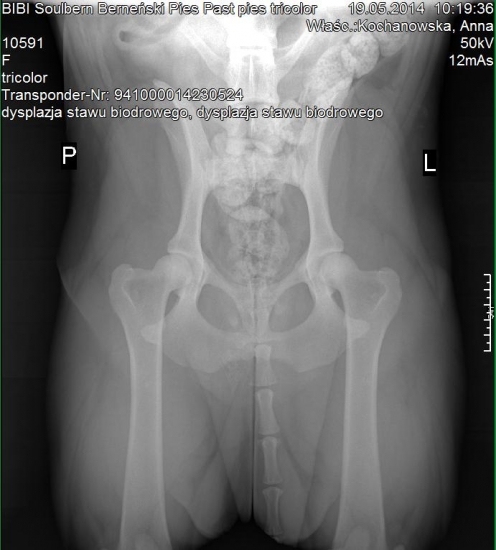

A ja mam kolejny powód do zadowolenia z moich Soulberniatek, w dniu dzisiejszym Bibi Soulbern przeszła pozytywnie, komplet prześwietleń pod kątem dysplazji stawów biodrowych, łokciowych i OCD stawów barkowych .

Bibi jest wolna od dysplazji z wynikiem HD A, ED 0/0, OCD neg. :-D :radocha2:

Bioderka HD A